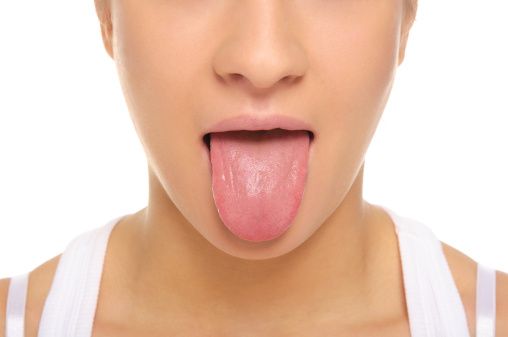

During a comprehensive dental examination, our team will look for signs of oral cancer. Early detection is key with oral cancer. If caught early, most forms of oral cancer are treatable. Our dental team is trained and educated to identify oral cancer.

Everyone is susceptible to the disease, but some groups of people are at a higher risk level than others. Here are the top seven risk factors for oral cancer.

Oral cancer does not discriminate. While these seven factors have been tied to an increased risk of oral cancer, that does not diminish the importance of regular oral examinations for everyone regardless of their age, gender, or other factors. Regular dental examinations make it possible for our team to detect oral cancer early. Contact our Lilly Family Dentistry Sioux City dentist to schedule a comprehensive oral examination.